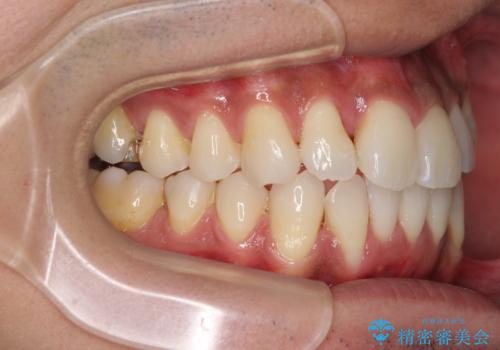

上顎の狭い歯列をインビザラインで拡大

- 上下前歯の叢生を気にして来院された患者様です。

奥歯はクロスバイトとなっているので上顎は側方拡大を行いつつ、上下全体の叢生をインビザラインにより改善することとしました。

治療途中でクリーニングやホワイトニングを行い、歯列が整うと同時に明るい口元となりました。